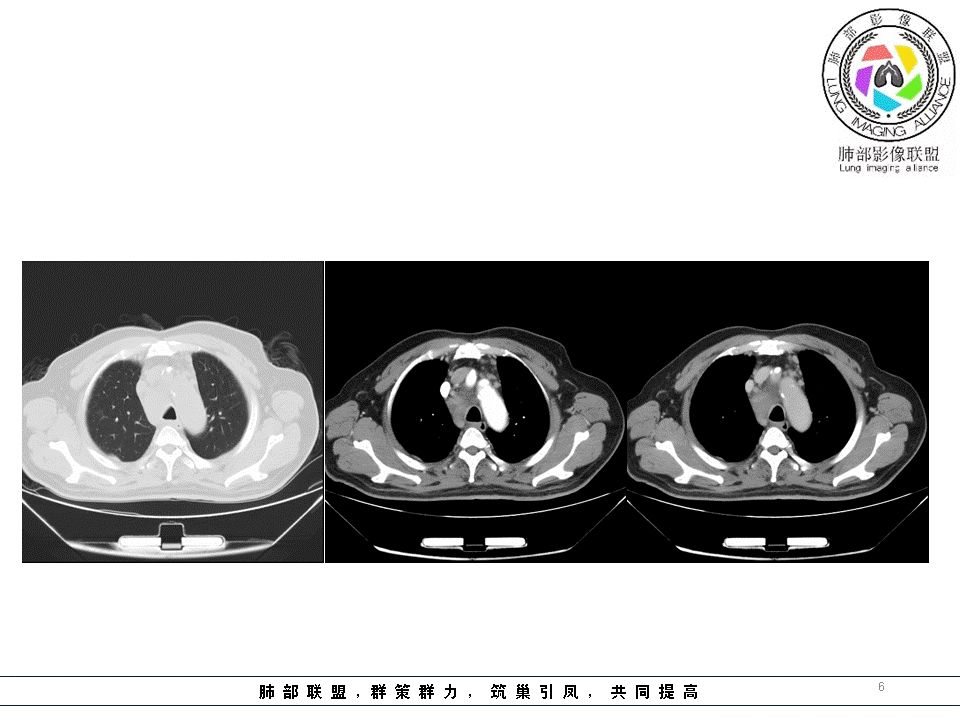

南边:临床:老年男性,病史偏长,2月。临床有通气功能障碍。

我们看影像,肺内有一些小斑点状高密度影,部分区域有气体潴留:

南边:我们现在影像上看的,也就是肺部小斑点,这些斑点,有些地方有气道储留的一个特点。

南边:但是我们看纵隔就多发的肿大淋巴结,部分融合成团。

南边:而且这些淋巴结,有些直接主要是压迫支气管壁,但是有些是突入到支气管腔内的。可惜我截的图发不上来。就左上舌段,支气管壁明显的增厚。有些明显腔内突的一个结节的,但是远的没有阻塞的特点。南边:增强以后呢,这个病灶明显强化,部分的似乎有环形强化的迹象,但不是很典型。

我们看这个主支气管的层面,主支气管明显受压,有变形的,但是软骨是没有突破的。

南边:那也就是说,这个纵隔淋巴结,它是没有影响到我们主支气管内部去的,周围有,可惜的膜部的增厚,我总心里不踏实,后面因为食道贴在一起啦。 因此这些淋巴结在主支气管层面是没有影响的。

这个区域明显就是一个支气管本身有问题。

但是有一个地方有问题的,左侧的上叶的下舌段这个区域:

左上叶舌段这个气管腔内是有东西凸进去。

首先弥漫性的,支气管壁是一个问题,然后有病灶凸向腔内,那又是一个问题,我有两种想法。

1、支气管壁本身有问题,2周围淋巴结侵犯支气管壁